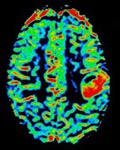

The one-year program provides advanced training in all neuroimaging modalities including advanced imaging techniques, such as CT and MR perfusion, MR spectroscopy, CSF flow imaging, diffusion tractography, and functional MRI. Fellows will also be exposed to advanced nuclear medicine techniques by way of multidisciplinary conferences, including brain PET with various clinical and investigation radiotracers due to the availability of an advanced cyclotron and integrated PET/MR. The close clinical and research relationship with various clinical departments results in exposure to the most advanced neuroimaging techniques in epilepsy, brain tumors, and neurodegenerative disease, amongst others. The program is a well-rounded and varied experience that can serve as a solid foundation for either academic or private practice careers.

Over 10 CT scanners are operated by the department ranging in detector size up to 256-slice. Additional capabilities include whole-brain perfusion imaging and dual energy acquisition.

UAB also houses the T24 cyclotron, the most powerful of any academic medical center in the United States. The cyclotron is located adjacent to two state-of-the-art PET/CT scanners and an integrated GE PET/MRI allowing the simultaneous acquisition of PET and 3T MRI data. UAB is involved in numerous clinical studies in investigational radiotracers in neuroimaging including uses in neurodegenerative diseases and brain tumors. The nuclear medicine faculty work closely with the Neuroradiology faculty, including multidisciplinary conferences.